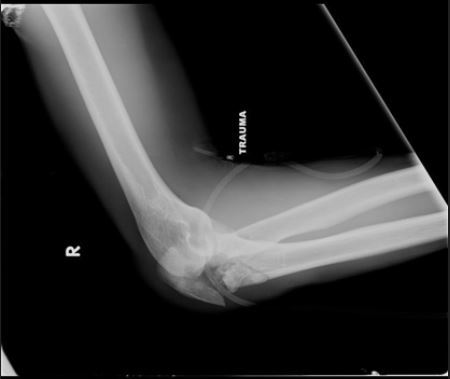

What is the most common complication of the fracture seen in figure A, if operatively treated as seen in figure B?

decreased elbow range of motion